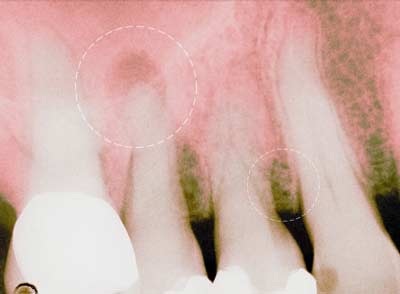

Đau răng có thể là do sâu răng, bị áp xe răng hay các vấn đề khác